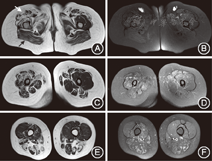

患儿 女,9岁,主因"肢体无力2年3个月余,加重7个月"于2018年1月就诊北京大学第一医院。患儿早期智力、运动发育正常。5岁9月龄起无明显诱因在做操时发现双上肢上举费力,右侧为著,当时双下肢活动尚可,跑跳正常。当地医院查血清肌酸激酶(creatine kinase,CK)466 U/L(正常值25~170 U/L);血串联质谱分析、尿气相色谱-质谱分析、肌电图、头颅磁共振成像(magnetic resonance imaging,MRI)、脊髓MRI及肺功能均未见异常,未予进一步诊治。患儿双上肢无力呈缓慢加重,至8岁5月龄时,双上肢无力明显加重,刷牙、举杯喝水均费力,穿衣困难,并出现双下肢无力,表现为跑跳差、蹲起费力、上楼梯困难,右侧肢体无力较左侧著。至9岁时进展至走路易摔倒、平卧位不能自行坐起。病程中不伴有发热、皮疹,无呼吸困难、饮水呛咳及吞咽困难。既往史、个人史无特殊。家族中无类似患者,患儿弟弟5岁,体健。入院体格检查:神志清,反应可,心、肺、腹未见异常;走路不稳,Gowers征(+),左侧肢体近端肌力3级,远端肌力4级,右上肢近端肌力2级,右下肢近端肌力3-级,远端肌力4级,四肢肌张力减低,无共济失调体征,四肢腱反射均未引出,双侧巴氏征阴性。住院后复查CK 299 U/L;因考虑四肢肌力不对称,近半年病情进展较快,不除外炎症性肌病,查红细胞沉降率、免疫球蛋白、补体、自身抗体谱、甲状腺功能及甲状腺抗体均正常;肌炎相关抗体PL7抗体阳性(+++),余阴性;双侧臀部及大腿肌肉MRI提示水肿、脂肪浸润改变,左右病变不对称,右侧著,其中肌群受累呈选择性:闭孔内外肌、大腿后群(半膜肌、半腱肌及股二头肌)和部分内侧肌群(股薄肌)受累较重,而臀大肌未受累,大腿前群肌肉(股中间肌、股外侧肌、股内侧肌、缝匠肌)受累较轻(图1)。肌电图显示左肱二头肌运动单位电位时限缩短,提示肌源性损害可能性大。进一步行左肱二头肌活检光镜下显示多灶性分布的肌肉萎缩、不同程度坏死和再生,肌纤维内不规则空泡和嗜酸性胞质体,不能除外炎症性肌病(图2);主要组织相容性抗原-Ⅰ(major histocompatibilityantigen-Ⅰ,MHC-Ⅰ)免疫组织化学染色示部分萎缩肌纤维呈阳性表达,亦提示炎症性肌肉病理改变可能。

治疗及转归:结合患儿肌肉MRI和肌肉病理,考虑"炎症性肌病"可能性大,但患儿病程较长,不能除外遗传性肌病,故同时送检家系全外显子基因测序以协助诊断。给予丙种球蛋白(2 g/kg)静脉输注、甲泼尼龙冲击[20 mg/(kg·d)×3 d]并序贯足量泼尼松口服、辅酶Q10口服,辅以康复训练,患儿走路姿势略好转。但患儿出院后1个月随访,病情未进一步好转。此时家系全外显子测序回报,示FHL1基因c.311G>A,p.C104T,为已知杂合新生致病性变异,父母均为正常基因型(图3)。进一步对患儿肌肉活检组织进行甲萘醌-硝基四氮唑盐(menadione-nitrobluetetrazolium,M-NBT)染色,胞质内可见蓝紫色包涵体(图2);肌肉电镜发现肌膜下及肌原纤维之间大量高嗜锇颗粒,部分形成大的包涵体,可见少数指纹样小体(图4)。根据M-NBT染色见蓝紫色包涵体,及FHL1基因发现致病性变异,最终确诊还原体肌病。减停泼尼松,继续康复训练,定期随访1年半,患儿肢体无力呈缓慢加重,尚可独走,但较易摔倒。

还原体肌病是一种罕见的肌原纤维肌病,致病基因FHL1位于Xq26,为X连锁显性遗传,其特征为肌纤维胞质内出现嗜伊红物,其内含丰富巯基,可将M-NBT还原为蓝紫色,因此命名为还原体肌病[1,2]。根据临床表现分为严重型(OMIM 300717)和轻型(OMIM 300718),其中轻型在儿童后期或成人期起病,表现为四肢或全身进展性非对称性肌无力。本例患儿肌无力为非对称性,以右侧为著,符合轻型还原体肌病的临床特点,但其起病相对既往文献报道的更早,且近期病情进展相对快,提示该疾病的病程进展可以是非匀速的。本患儿的肌肉MRI显示肌群受累具有选择性:闭孔内肌、大腿后群和部分内侧肌群受累重,大腿前群肌肉受累轻,而臀大肌未受累;这与Astrea等[3]总结的还原体肌病的肌肉MRI特点一致,可作为临床上诊断的重要线索。本例患儿肌活检光镜下病变呈局灶性分布,可见肌纤维萎缩、不同程度坏死和再生,该病理改变也可见于坏死性肌病。但本例患儿HE染色见胞质内大量嗜伊红团块,改良Gomori染色为紫色,M-NBT染色呈蓝紫色,为还原体肌病所独有[1,2,4],以此可与坏死性肌病相鉴别。另外,M-NBT在多数临床中心并非常规染色,因此当HE染色中见大量嗜伊红物时需要考虑到还原体肌病,并加染M-NBT。本例患儿电镜下可见肌膜下及核周大量高嗜锇颗粒、还原体及少量指纹样小体,符合还原体肌病的电镜特点[1,2,4]。但需要注意其电镜下表现异质性大,取决于疾病阶段:早期为肌膜下大量高嗜锇颗粒,之后逐渐形成椭圆形的颗粒状、微管状、多孔状结构,即还原体,严重者形成指纹样小体。本例患儿临床表现为儿童期起病的进展性肌无力,查体以近端肌无力为著,四肢腱反射未引出,辅助检查血清CK轻度升高,肌肉MRI及肌肉活检证实肌肉病变,故定位诊断考虑肌肉病变。定性诊断(1)免疫性:患儿既往发育里程碑正常,近期病情进展较快,肌无力呈不对称性,肌肉MRI提示肌肉水肿,肌活检提示坏死性肌肉病样病理改变,MCHC-Ⅰ染色呈阳性,均支持免疫性;但其发病较隐匿,免疫治疗无效,为不支持点;(2)遗传性:其发病隐匿,需考虑,但近半年病情进展相对快为不支持点。患儿病初误诊为炎症性肌病,在全外显子组测序发现FHL1基因新发变异,且为已报道致病性变异后,重新全面评估患儿,复习肌肉活检标本电镜所见,进一步行肌肉M-NBT染色,发现蓝紫色包涵体,最终确诊还原体肌病。本例患儿除典型还原体肌病表现外,还伴有一些类似炎症性肌病的表现,包括肌肉MRI显示肌肉轻度水肿、肌肉病理MCHC-Ⅰ染色阳性等,既往少见报道。但在Duchenne型肌营养不良、面肩肱肌营养不良等其他遗传性肌病中,也发现伴有非特异性炎症的表现,提示免疫反应可能一定程度参与了部分遗传性肌病的发病过程。本例患儿虽有类似炎症性肌病的表现,但起病相对炎症性肌病更隐匿,且对免疫治疗反应欠佳,考虑到临床表现不典型,送检家系全外显子基因测序,最终协助明确诊断。对于隐匿起病的不对称性肌无力,如肌肉MRI发现臀大肌未受累,大腿后群及内侧肌群受累较前群突出,需考虑到还原体肌病的诊断,肌肉病理中发现M-NBT染色呈蓝黑色的包涵体及FHL1基因检测发现特定位点变异可明确诊断。